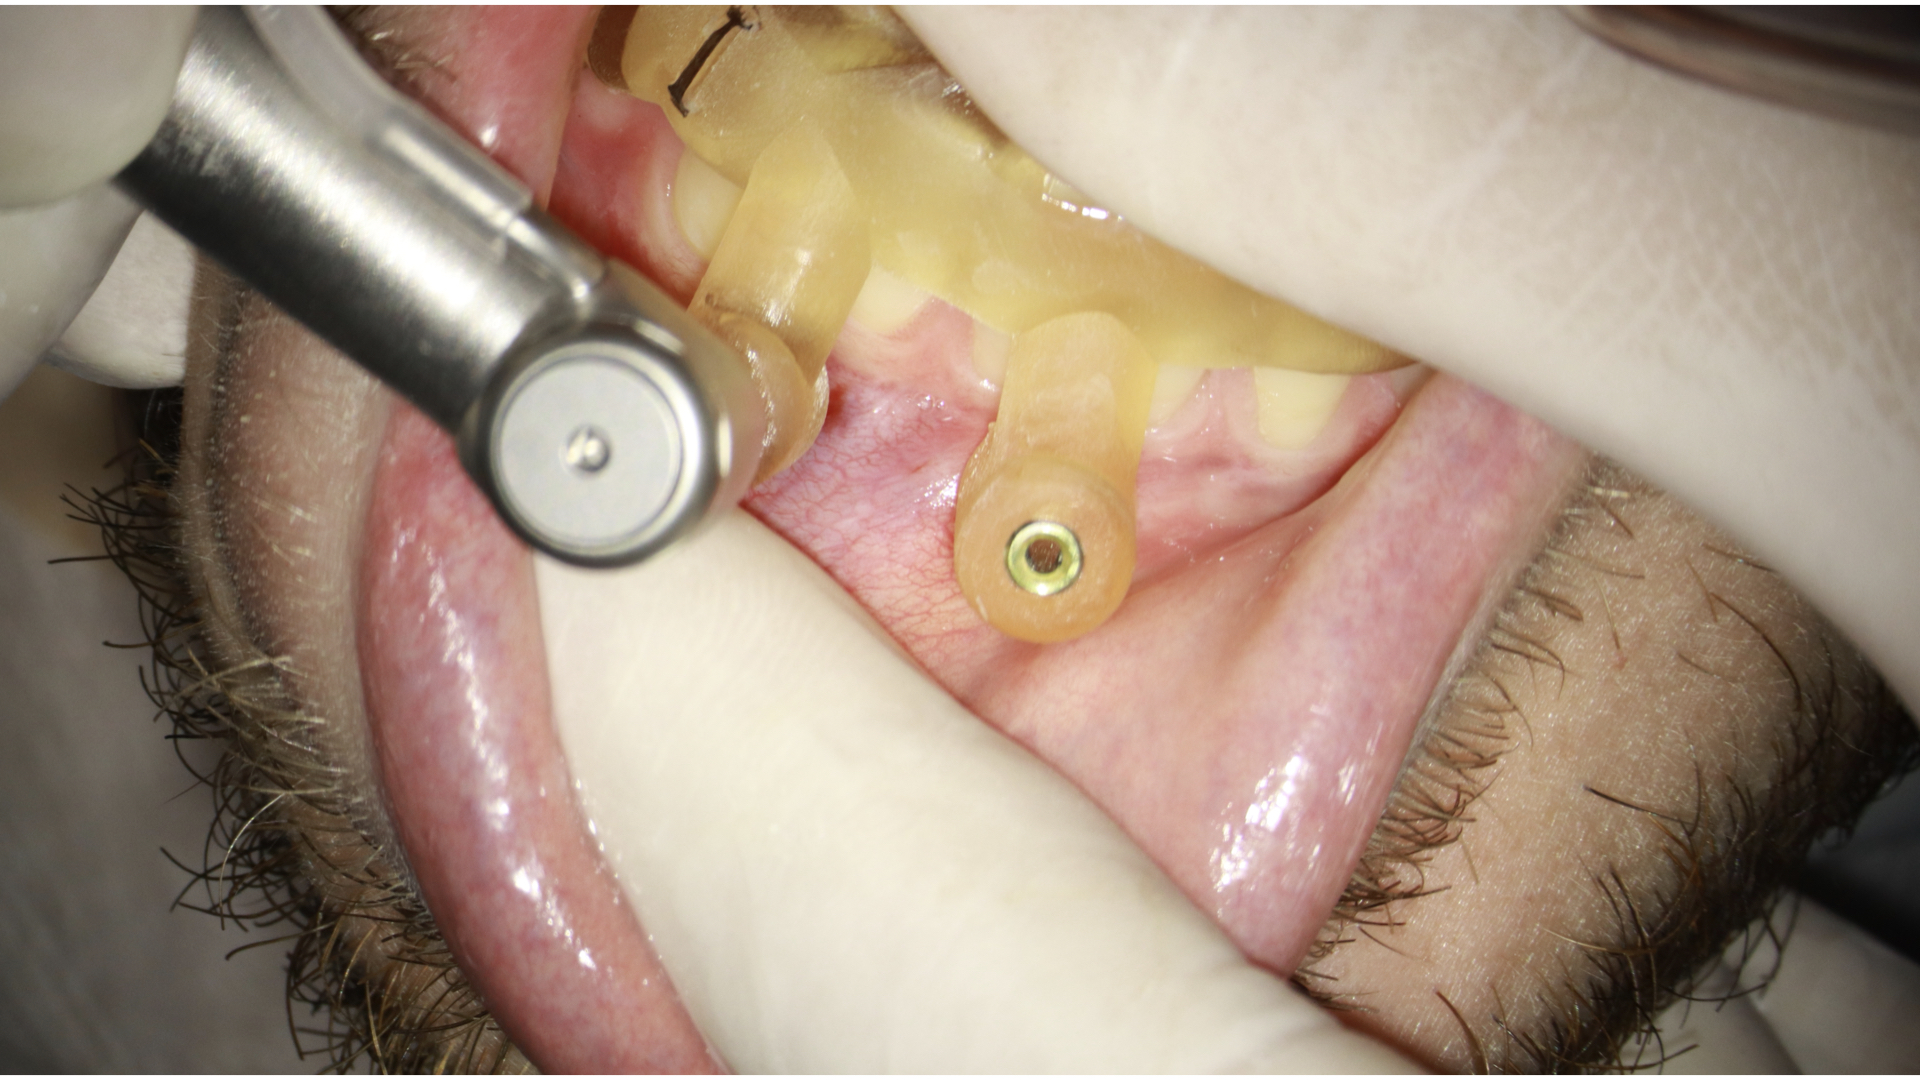

- Fixar o endoguide na arcada que necessita de tratamento com os fixadores. Estas anilhas usadas para a colocação da fresa e fixadores são metálicas. Para fazer está fixação é necessário o uso da fresa em osso. Você pode usar um motor endodôntico na máxima rotação e torque irrigando durante o procedimento ou um motor de implante que já tem a irrigação acoplada e facilita esta perfuração. A vantagem do motor de implante é que você consegue fazer a perfuração em osso com maior torque, o que possibilita que em caso de perfuração em mandíbula, com osso mais compacto, tenhamos um procedimento mais tranquilo (figura 7, 8 e 9).